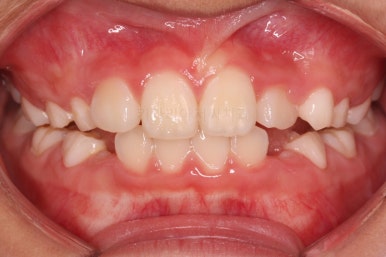

치료 시작 3개월째의 모습입니다.

윗니가 점점 앞으로 나오는게 보이실거에요. 사실은 치아가 나오는 것이 아니라 치아가 담겨있는 위턱뼈가 통째로 앞으로 나온 것입니다.

좀 더 하면 마무리를 할 수 있을 것 같네요.